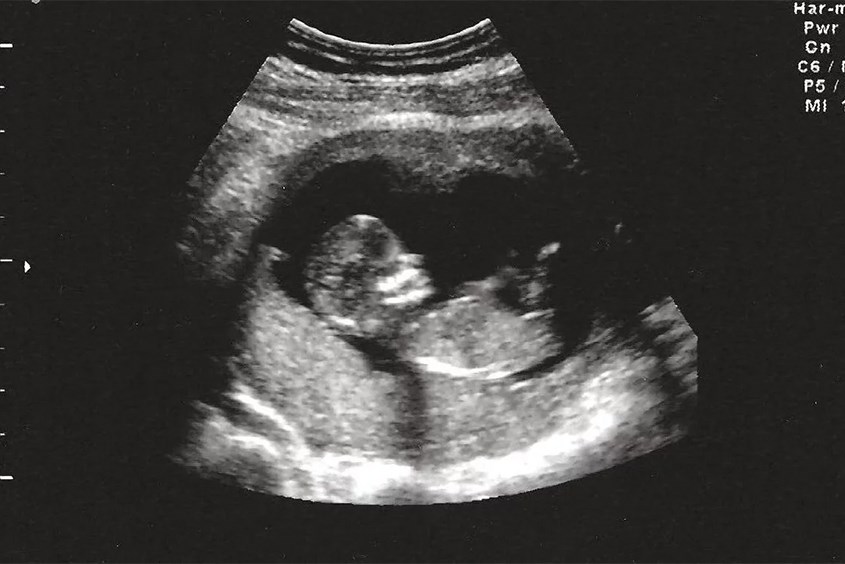

Hình ảnh siêu âm thai nhi 15 tuần tuổi

• Siêu âm thai: Giới tính của bé có thể được xác định khi mẹ bầu mang thai tuần 15 bằng phương pháp siêu âm. Tuy nhiên, nếu bé nằm chéo chân khi máy siêu âm lướt qua thì kết quả có thể vẫn chưa chính xác.